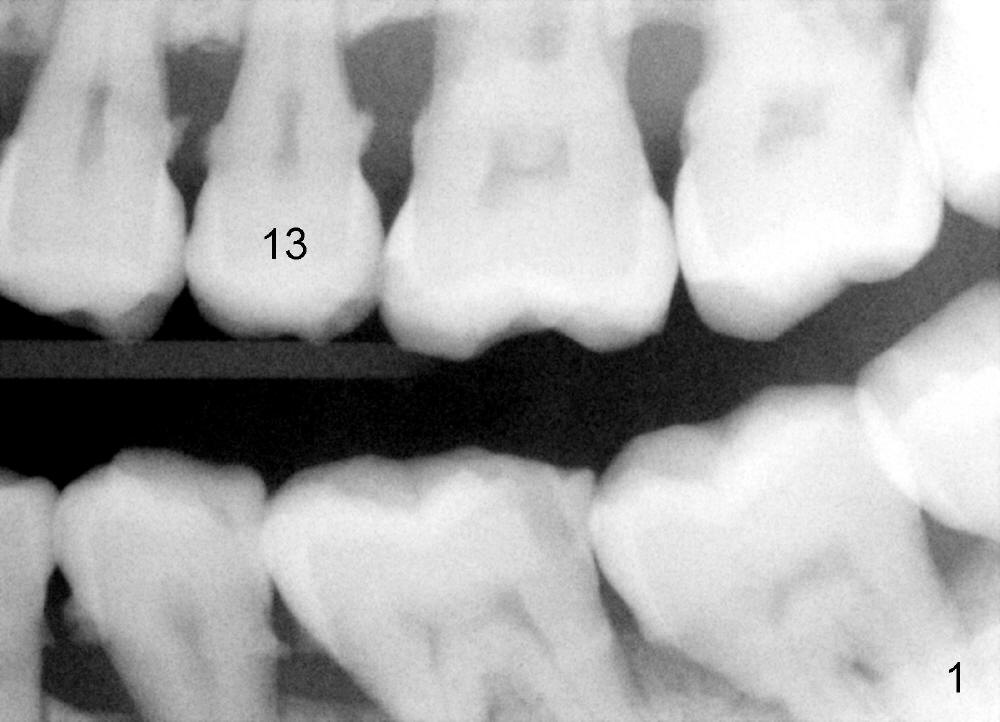

A 57-year-old man has history of chronic periodontitis (Fig.1,2, taken 9 and 7 years ago, respectively). Last April the tooth #13 had crown fracture (Fig.3). He returned to clinic for scaling & root planing last week (Fig.4). Fig.3,4 show long root and bone. Arrowheads in Fig.4 indicate the sinus floor.